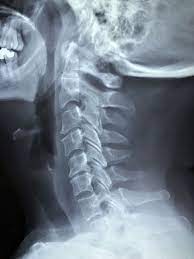

- X-레이 (X-ray): X-레이는 척추의 구조를 보는 데 사용됩니다. 디스크의 이상이나 척추 골절 등을 확인하는 데 도움을 줄 수 있지만, 디스크 자체의 세부 정보는 제공하지 않습니다.

- 자기 공명 영상 (MRI): MRI 스캔은 목 부위의 디스크와 주변 조직을 자세하게 보여줍니다. 디스크의 헤르니에이션, 디스크 디게너레이션, 신경 굴곡 등을 평가하는 데 주로 사용됩니다.

- 컴퓨터 단층 촬영 (CT 스캔): CT 스캔은 X-레이와 유사하지만 목 부위의 구체적인 문제를 더 자세히 보여줄 수 있습니다. 특히 디스크 헤르니에이션과 같은 구조적인 문제를 확인하는 데 유용합니다.